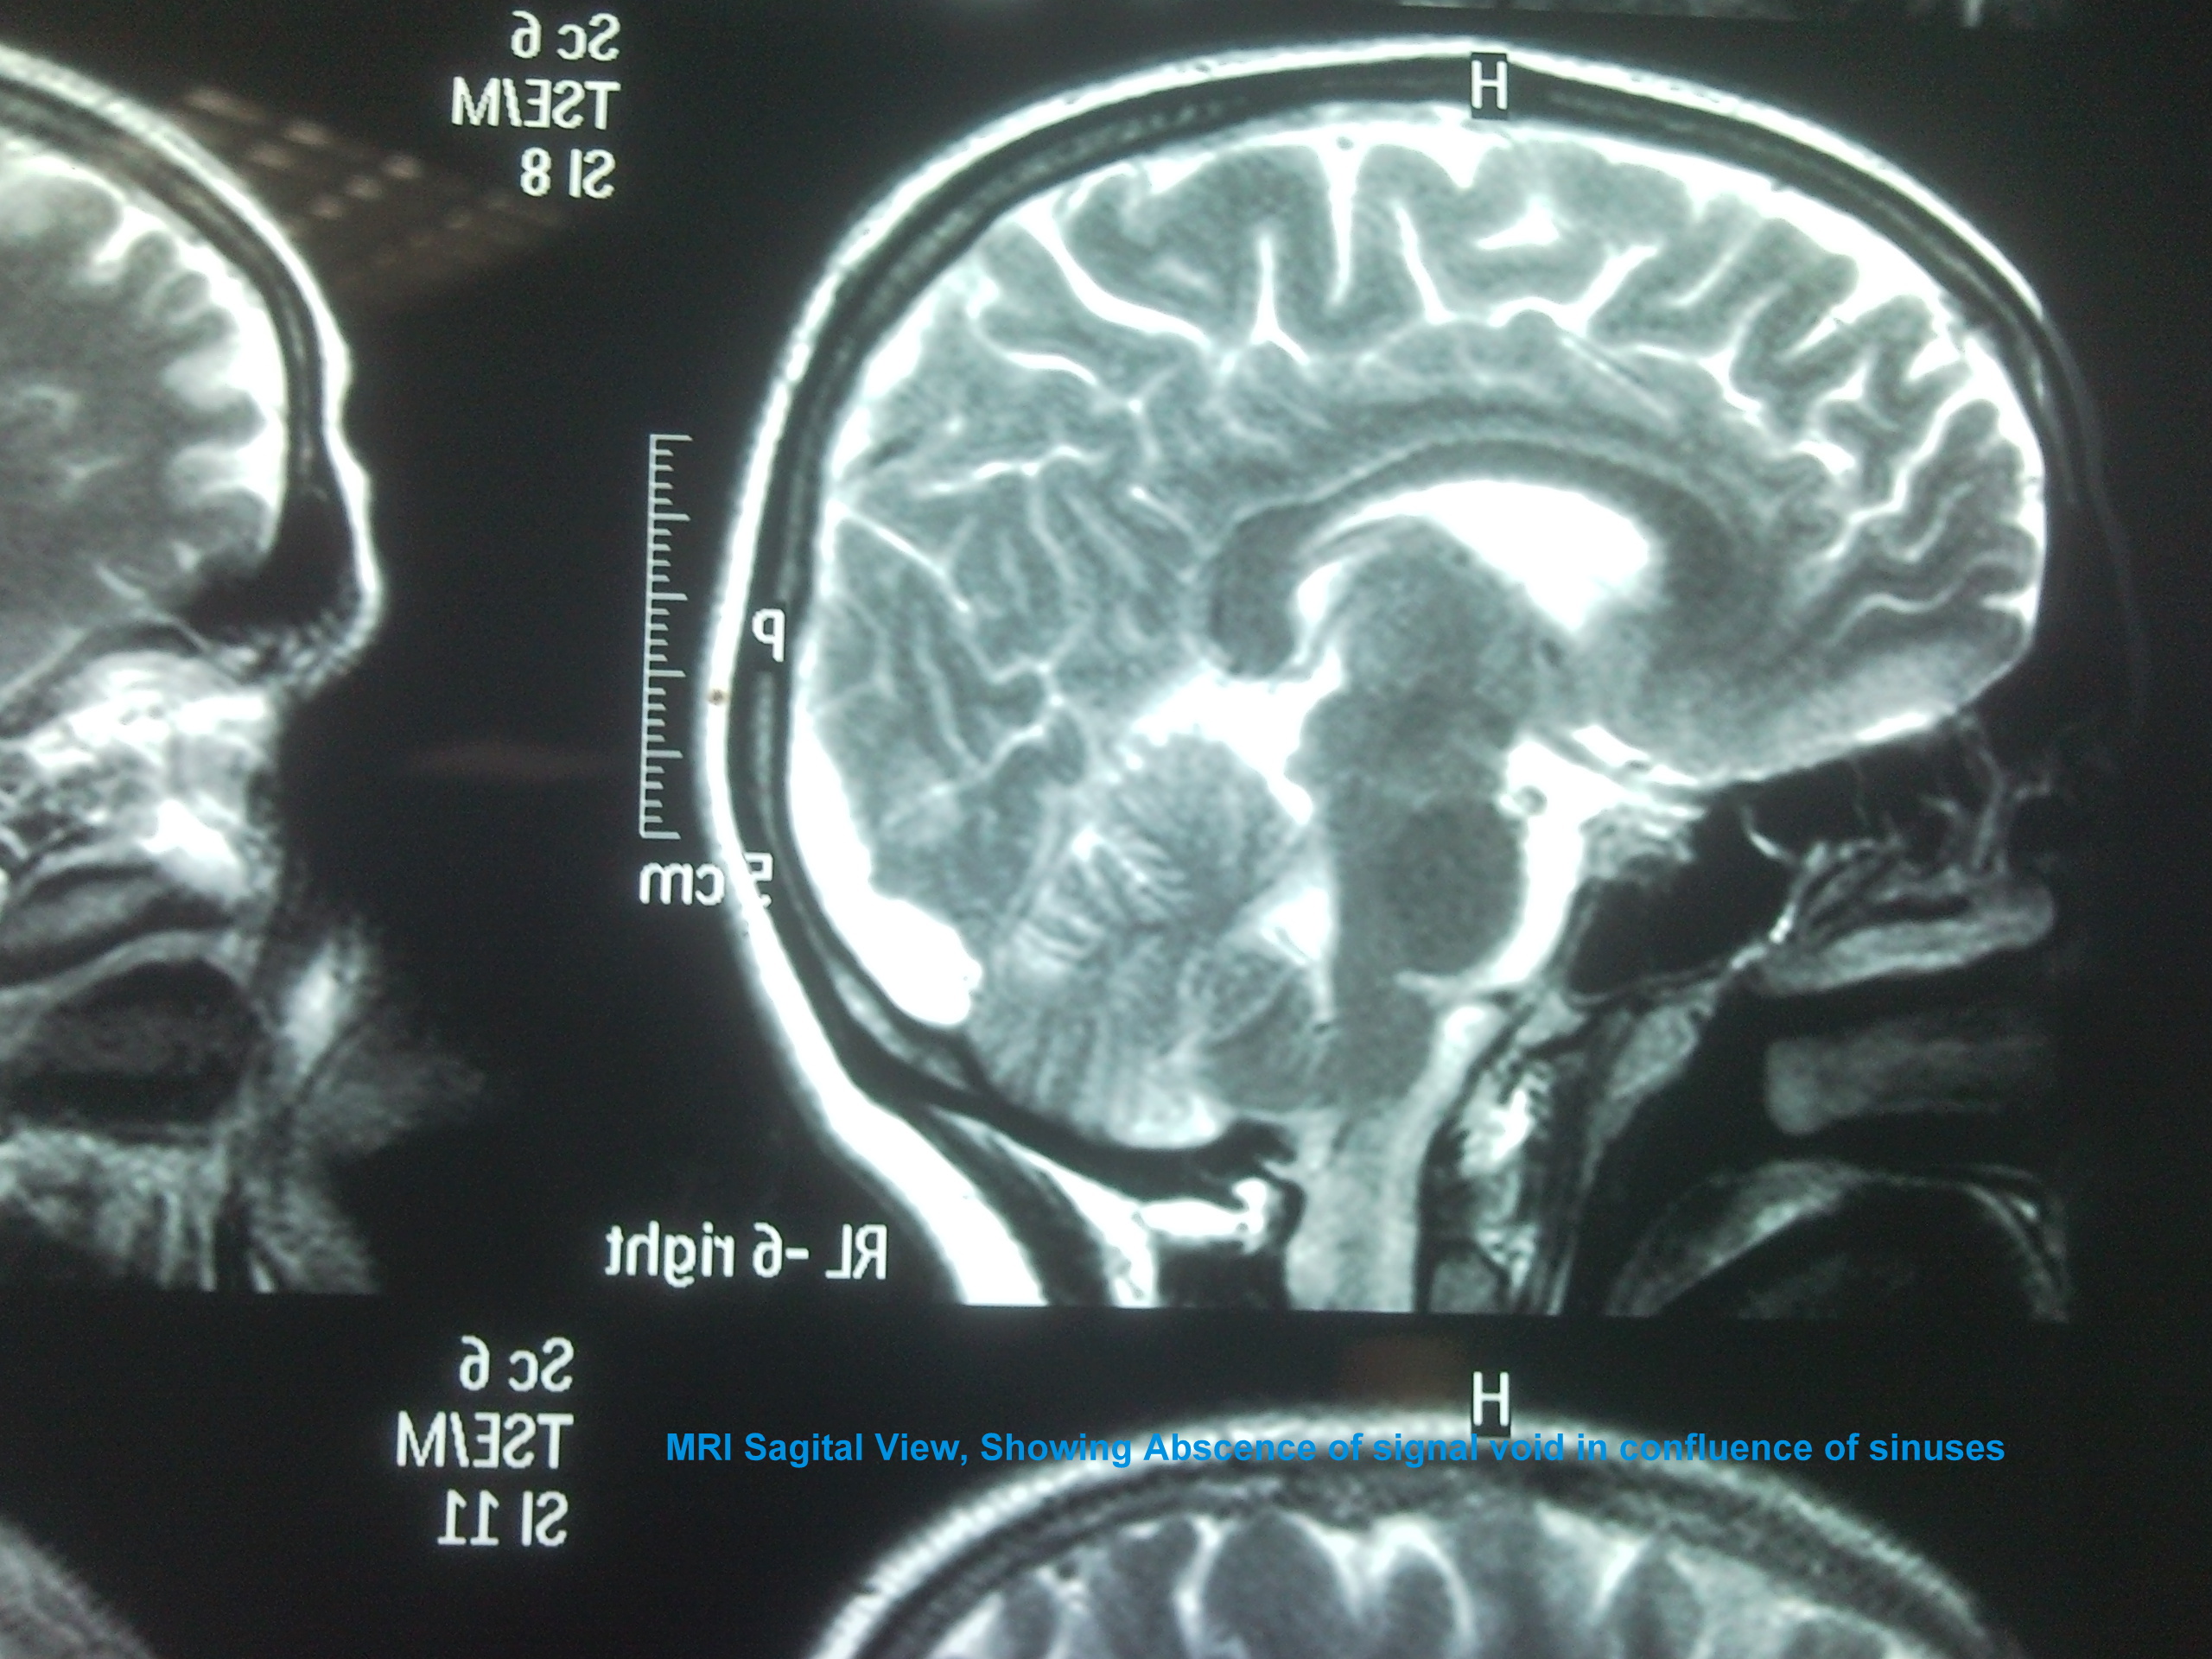

We present a case of 29 years old female patient with 20 days history of headache, projectile vomiting and low grade fever. She was referred from Swat where she was locally treated as acute pyogenic meningitis with no improvement. Patient had right 6th cranial nerve palsy and papilledema. CT brain was unremarkable and MRI brain with MR Venography showed superior sagital, confluence of sinuses and transverse sinus thrombosis.